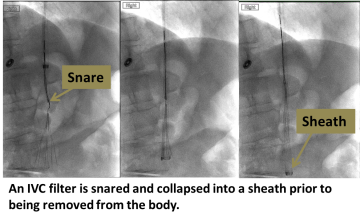

An interventional radiologist uses ultrasound to access the jugular vein at the neck. A snare is used to engage the hook at the top of the filter, and a sheath is passed over the filter to collapse and remove it. Sometimes more advanced maneuvers are required for filter removal.